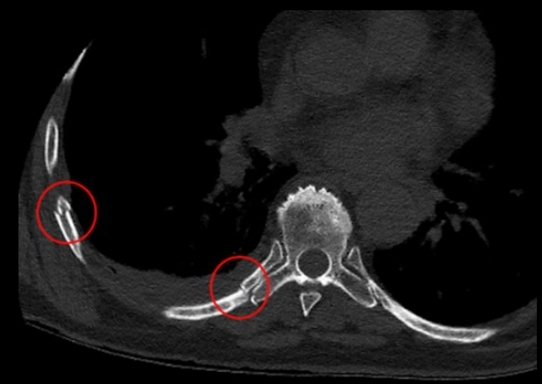

Mejor estudio para ver fracturas costales

TC

- Reconstrucción 3D

- Detecta fracturas no desplazadas

- Permite evaluar complicaciones fácilmente